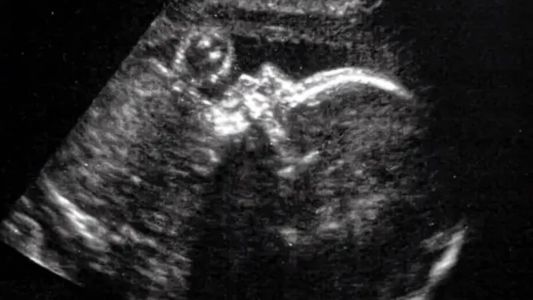

Uma cirurgia cerebral inédita, feita dentro do útero materno, salvou a vida de um bebê diagnosticado com uma doença genética mortal. O caso foi registrado nos Estados Unidos e sucesso da cirurgia foi divulgado nessa semana. O bebê foi operado com uma malformação aneurismática da veia Galeno, com 34 semanas e 2 dias de idade gestacional.

A cirurgia, realizada com 34 semanas e 2 dias de idade gestacional, foi documentada em um estudo de caso publicado na revista Stroke da American Heart Association, conforme informações do New York Post.

Uma equipe do Boston Children's Hospital e do Massachusetts General Hospital realizou o procedimento no feto, cortando o útero, depois o crânio do bebê e, por fim, operando o cérebro em desenvolvimento. Depois de cortarem o abdômen da gestante, eles usaram um ultrassom para localizar a artéria do bebê e ajudar no procedimento.